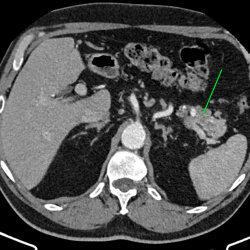

Здравствуйте, женщина 40лет, жалобы на увеличение живота, началось с 2023 года, жалобы на запоры временами и на водянистый стул, подскажите что здесь в области баугиниевой заслонки? ...

Здравствуйте, подскажите пациент 60 лет, особо жалоб нет, на узи было изменения в печени, в хвосте поджелудочной железы отмечаются немного гиподенсивные изменения может ли это быть раком? на МРТ...